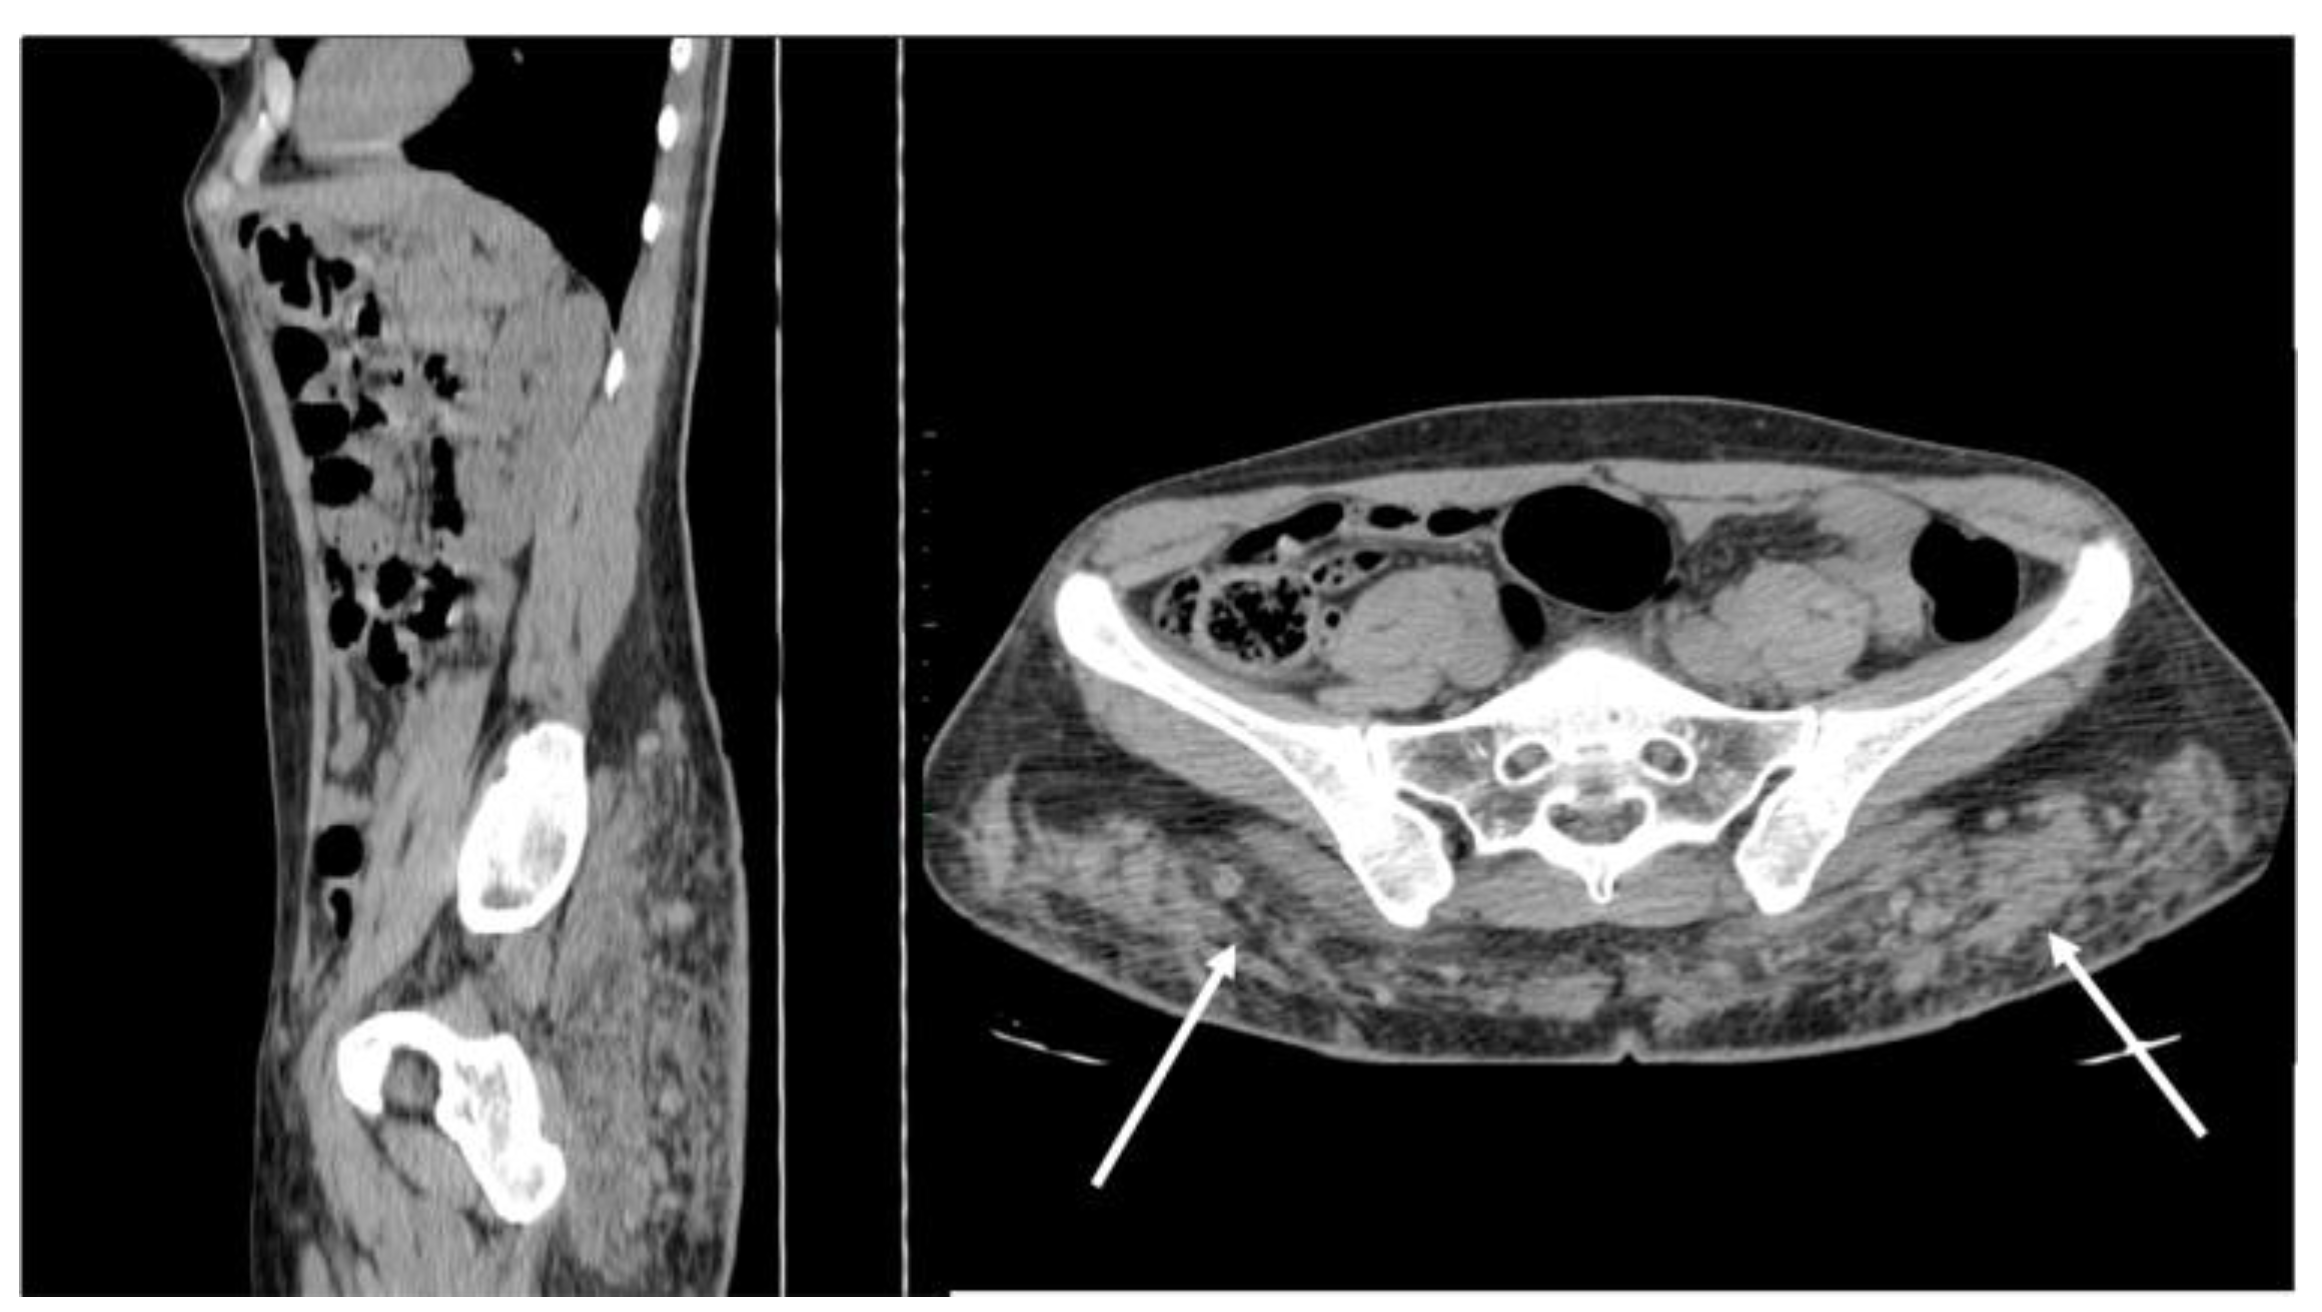

Figure 13. Non-enhanced sagittal and axial CT scan demonstrates free silicon material scattered with an infiltrative appearance, expanding all along the subcutaneous fat of the posterior abdominal wall (arrows). Strand-like lesions coexist with nodular and plaque-like areas, making the differential diagnosis with neoplastic conditions difficult.